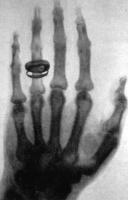

Bức xạ X là một dạng của sóng điện từ. hầu hết tia X có dải bước sóng trong khoảng từ 0,01 đến 10 nano mét tương ứng với dãy tần số từ 30 Petahertz đến 30 Exahertz và có năng lượng từ 120 eV đến 120 keV. Trong nhiều ngôn ngữ, bức xạ X được gọi là bức xạ Röntgen, được đặt tên theo nhà khoa học người Đức gốc Hà Lan Wilhelm Röntgen, ngay sau khi ông khám phá ra một loại bức xạ mà chưa ai biết đến.